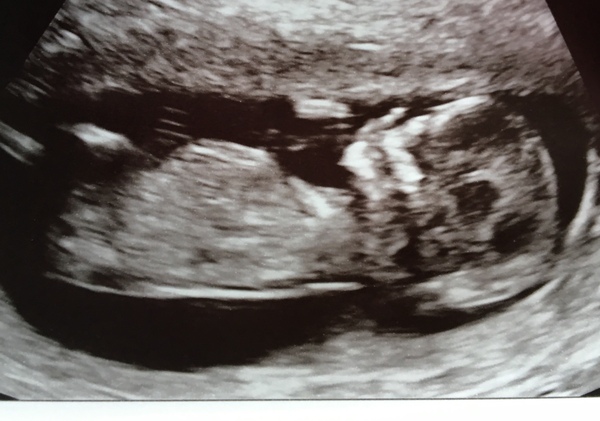

Here's my pic. I'm pretty sure it's a boy but not going to find out. Don't mind either way and would like a surprise!